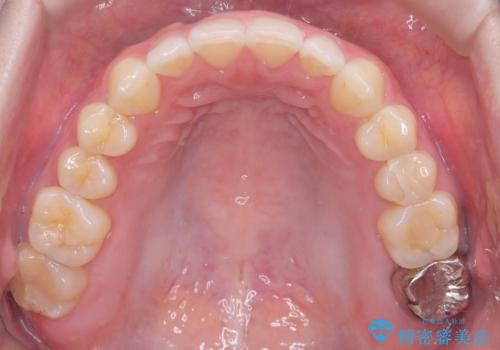

すきっ歯・切端咬合・空隙歯列|インビザラインで11ヵ月で治療完了

- すきっ歯と切端咬合(上下の前歯が先端で当たるかみ合わせ)を主訴にご来院された患者様です。

矯正検査を行った結果、非抜歯でインビザラインによる治療が可能と判断し、マウスピース矯正で改善を行いました。

11ヵ月で矯正治療が終了し、前歯の隙間も改善、見た目とかみ合わせも良好な状態となり、患者様にも大変ご満足いただけました。